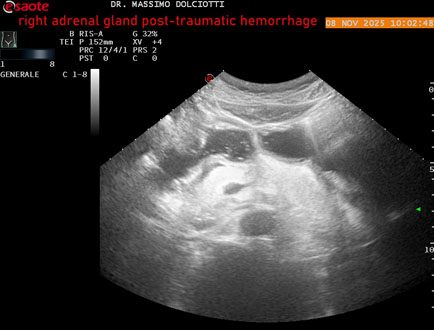

Data inserimento: 10/11/2025

Ecografia del: 08/11/2025

Strumento: Esaote MyLab Eight

Sonda: Convex Multifrequenza 1-8 MHz

Età Paziente: M 49 anni

Motivazione dell'esame: follow up per emorragia al surrene destro post-traumatica (incidente stradale).

Commento all'esame: le immagini ed il video documentano in sede surrenalica destra, formazione ipo-anecogena, a margini definiti, ovalare, delle dimensioni di 38,6 x 19,7 mm, da ricondurre ad emorragia post-traumatica.

Conclusioni: emorragia post-traumatica al surrene destro (post-traumatic hemorrhage to the right adrenal gland).

Presentazione: Dr. Massimo Dolciotti - Ancona

Elaborazione digitale: Andrea Dini - Ancona